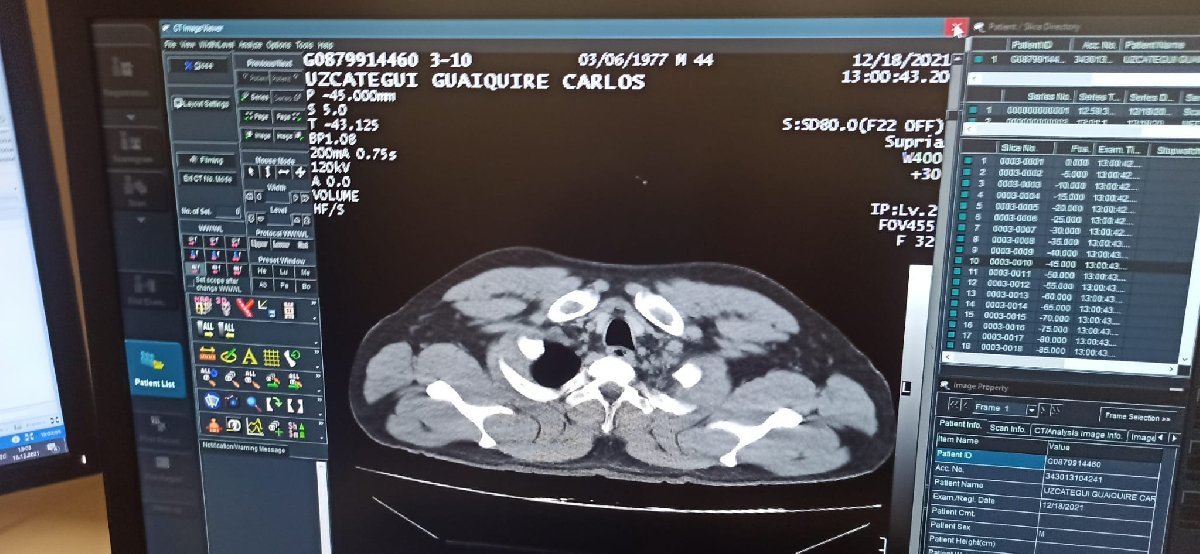

Yapılan ilk muayenenin ardından C.M.U.G., tedavisi için havalimanı emniyet şube müdürlüğü ekiplerinin kontrolünde hastaneye kaldırıldı. C.M.U.G’un hastanede yapılan tomografi kontrolünde mide ve bağırsaklarında 12 adet kapsül kokain tespit edilmesini üzerine, ameliyata alındı.